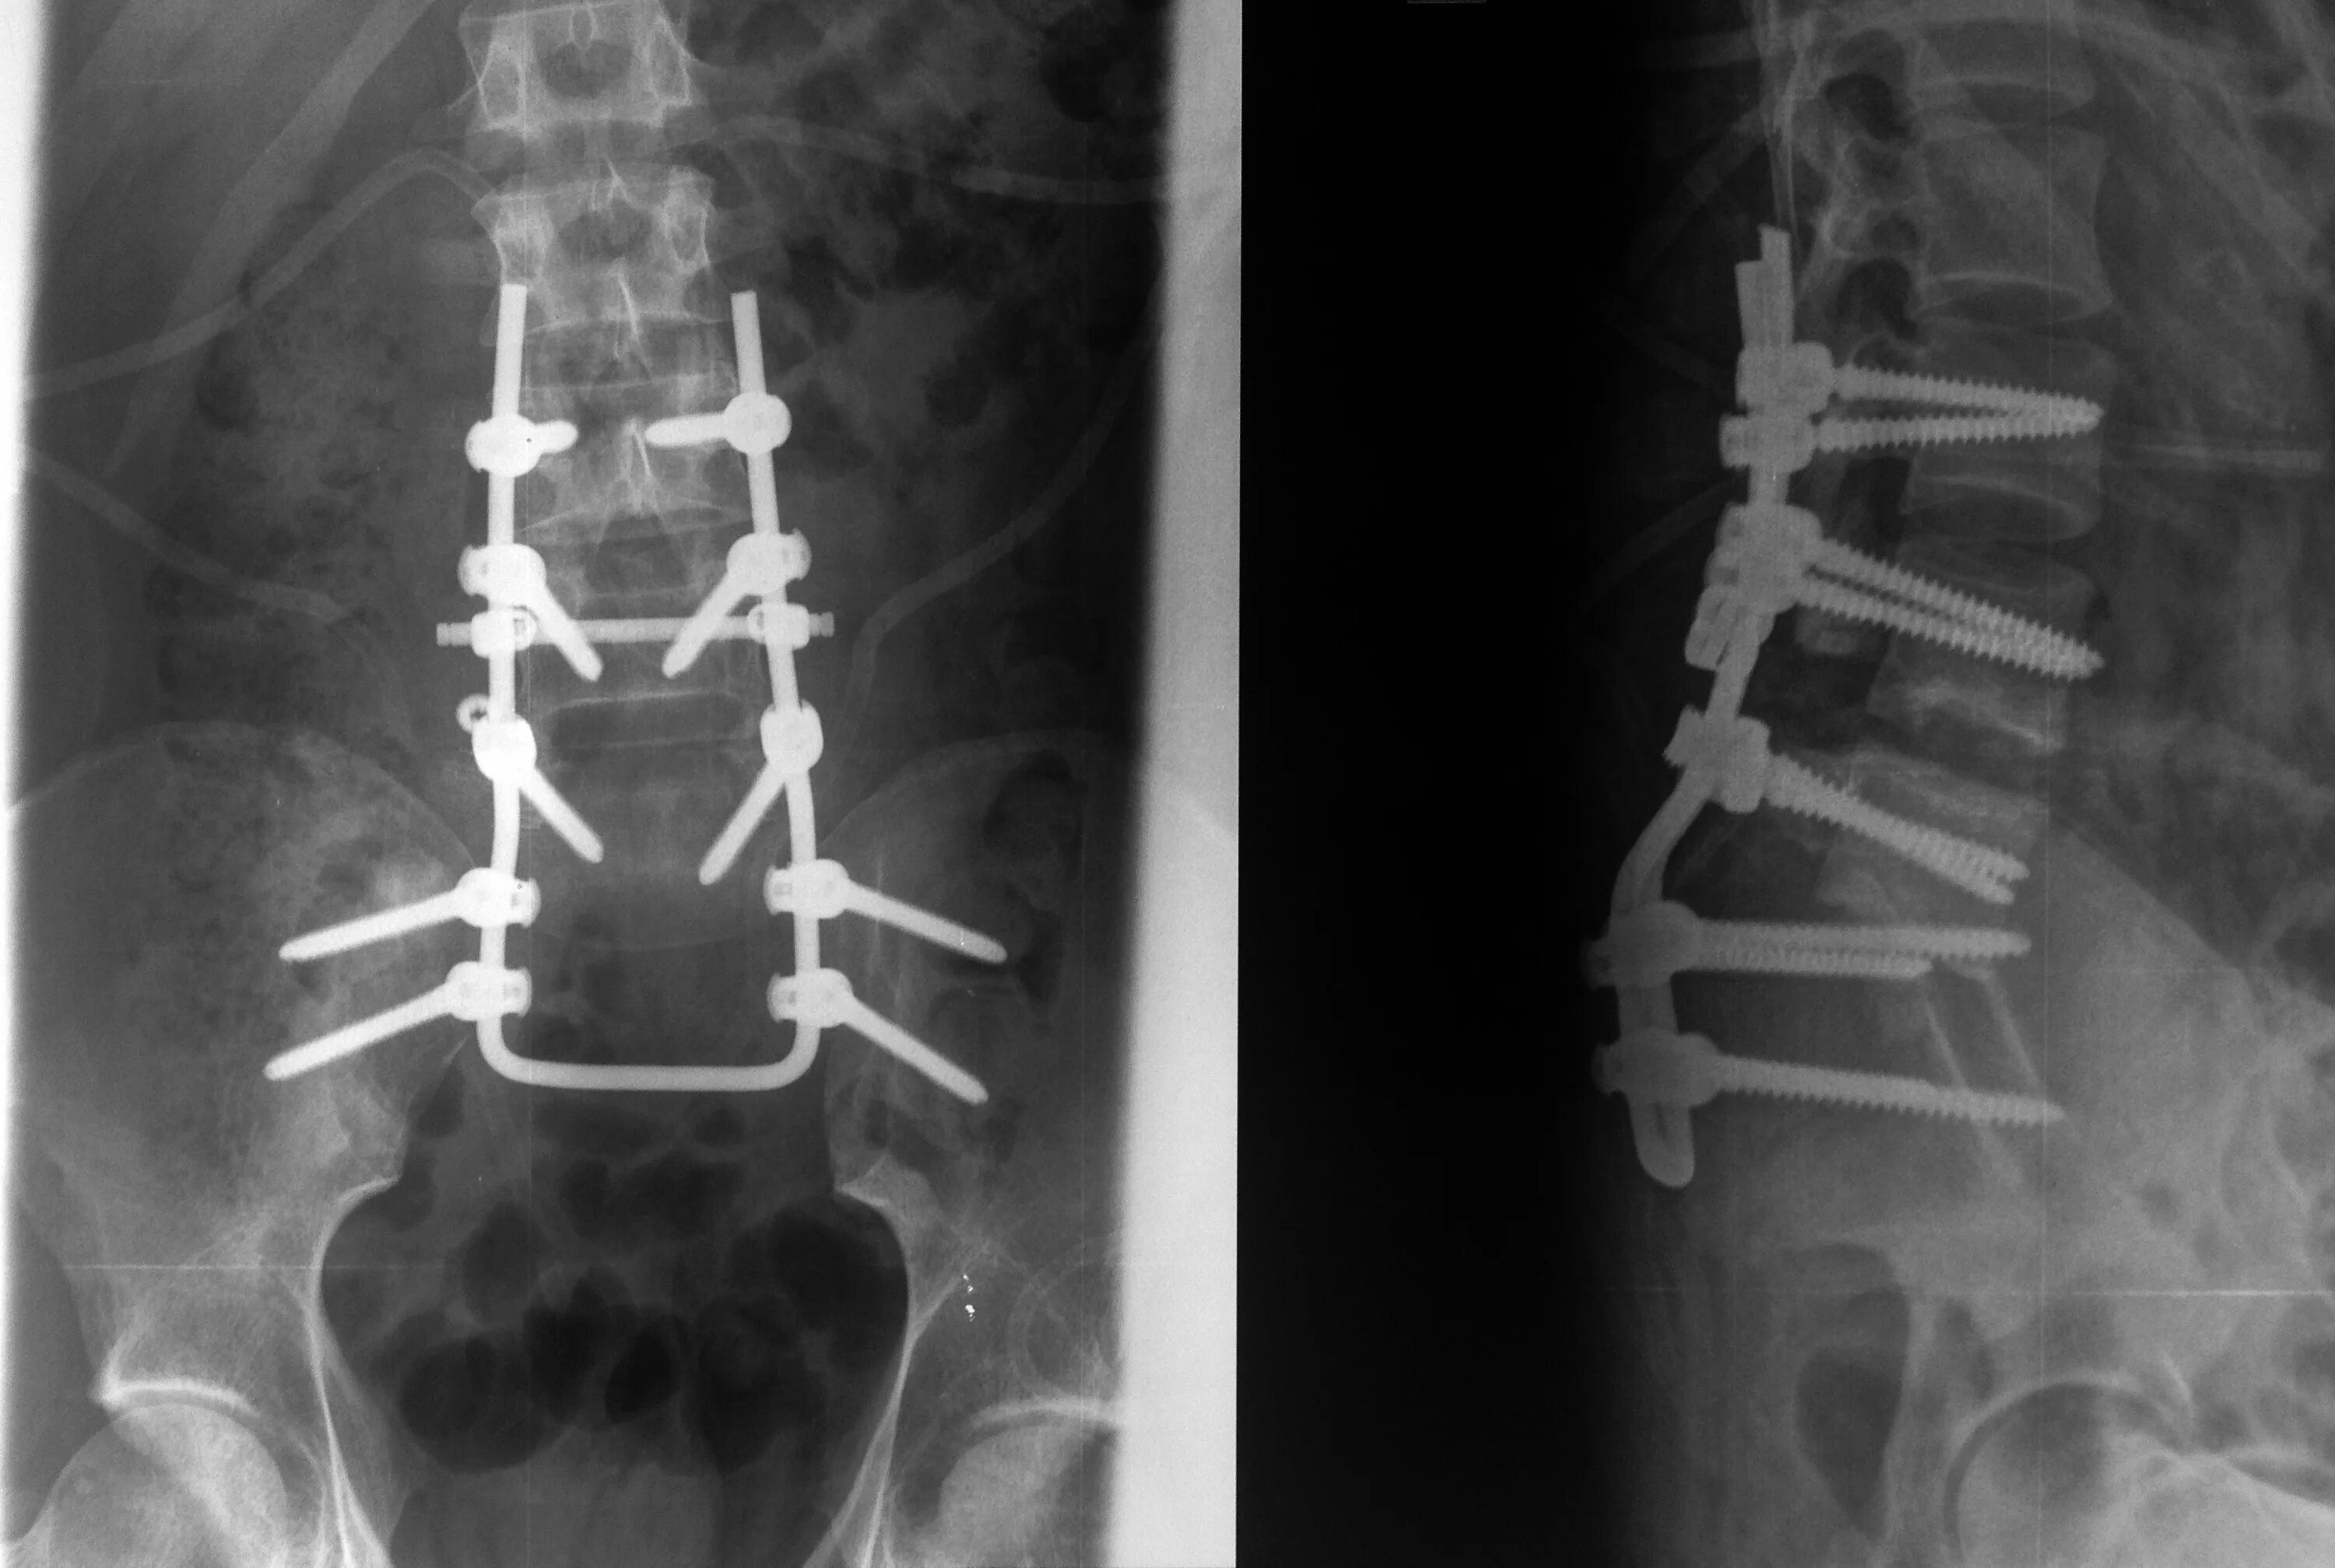

Метастазы в крестце